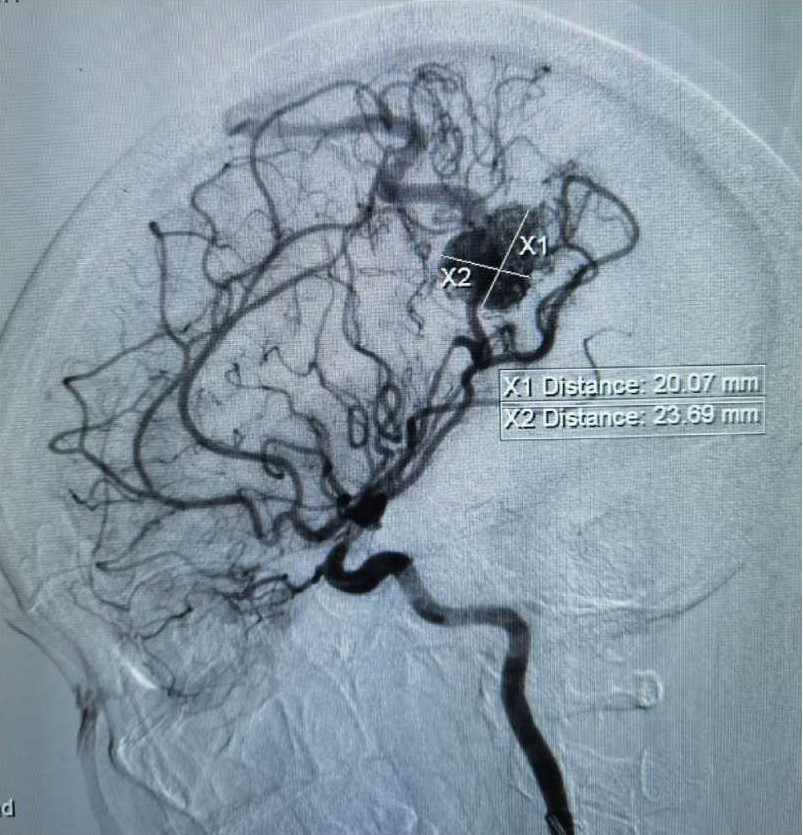

行DSA检查

显示畸形血管团为20*23mm,多支动脉参与供血,引流至上矢状窦。